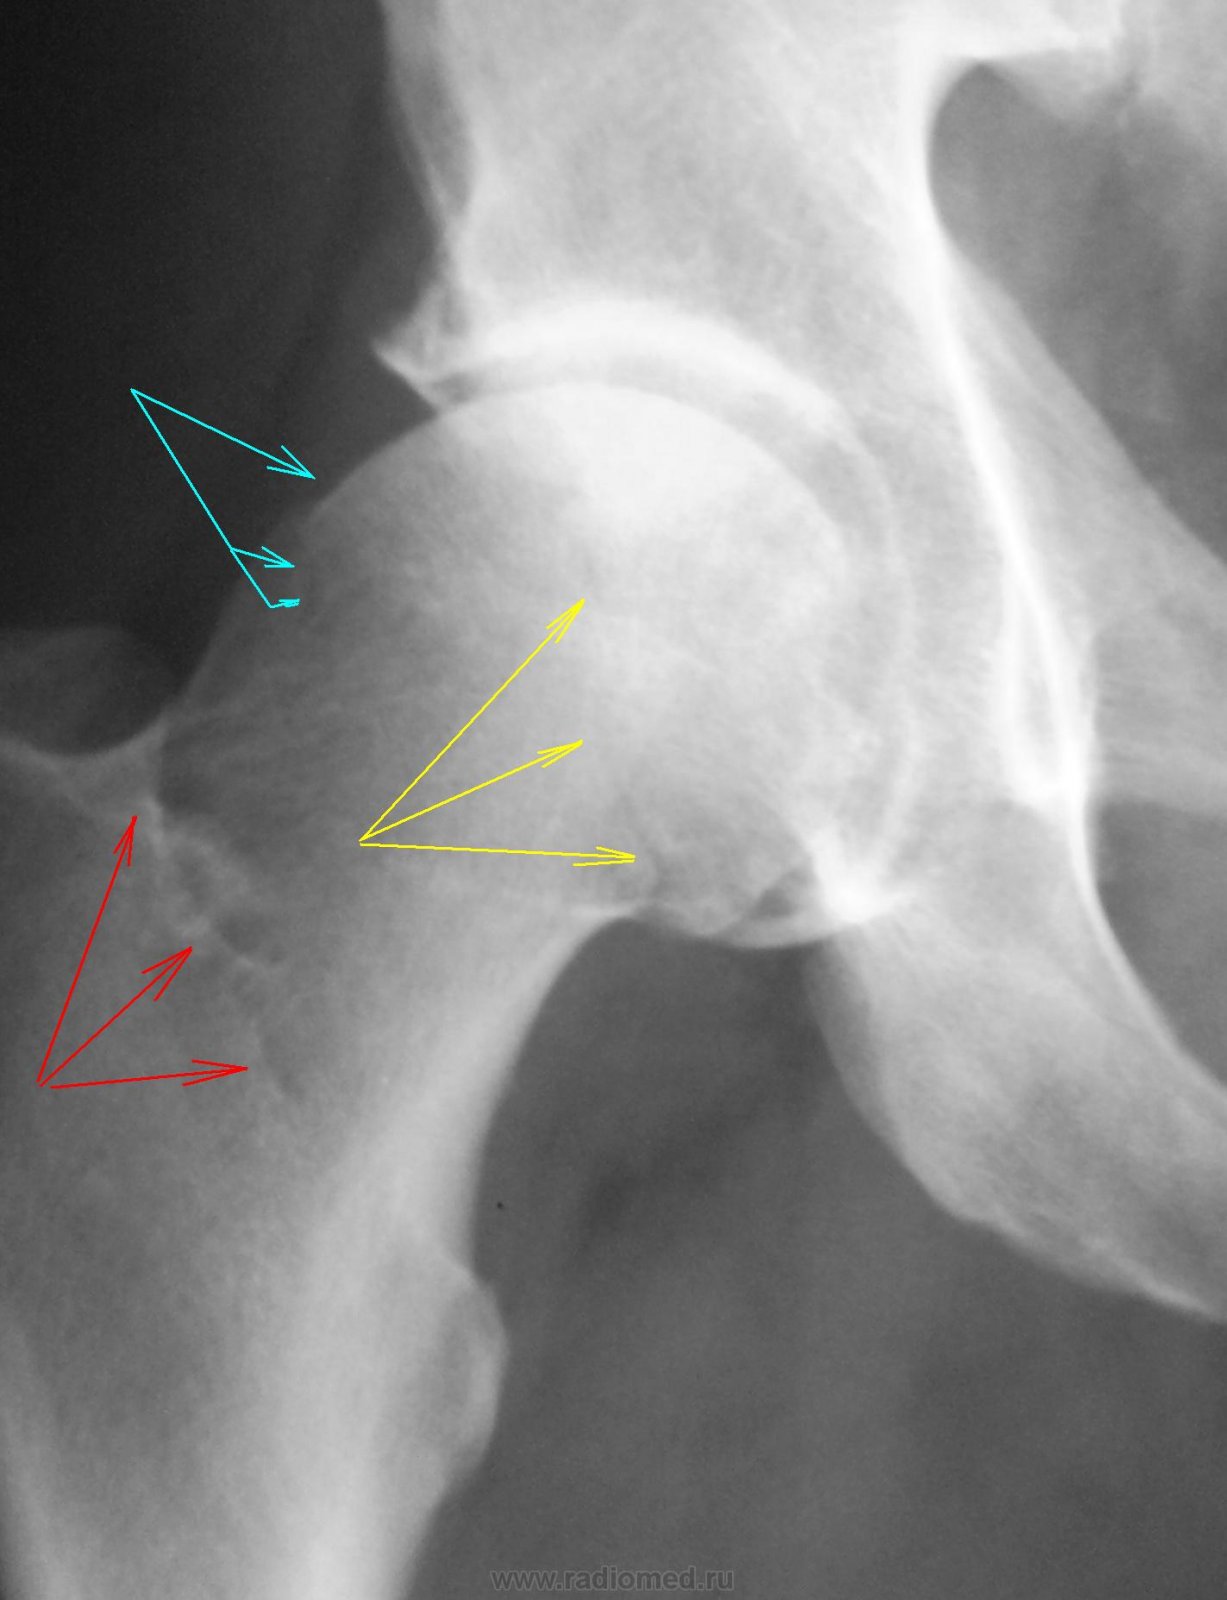

Рентгеновские снимки анкилоза суставов: Как это выглядит